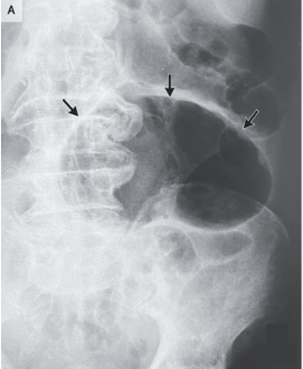

9歳男児。1年前から発疹と3ヵ月前からの腹痛と下痢を訴え小児科を受診した。 生後6か月の時点で原因不明の亜鉛欠乏症のため、以降経口Zn補給を受けている。 201…